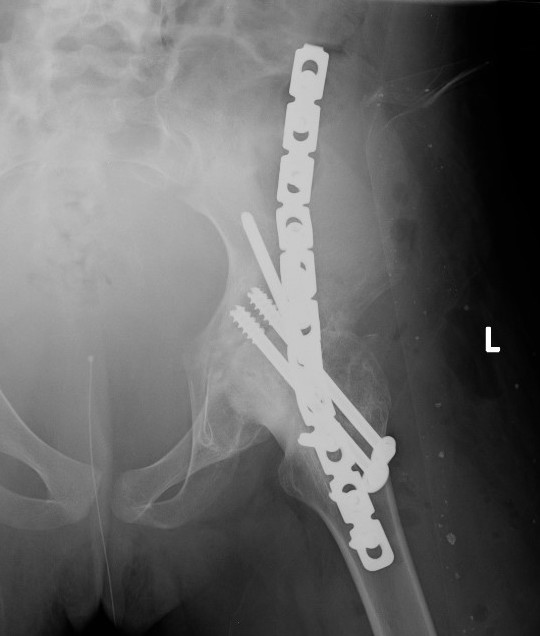

Extra-articular Intra-articular Combined intra-articular + anterior plate

Hip Fusion Cobra Plate Hip Fusion AP Hip Fusion 1Hip fusion 2

Fixation

- 150° DHS / 6.5 mm cannulated screws

- through joint into thick supra-acetabular area of ilium

- supplement with additional screws as necessary

Anterior plate onto lateral aspect of iliac crest

Consider late plate removal to reduce risk peri-prosthethic fracture